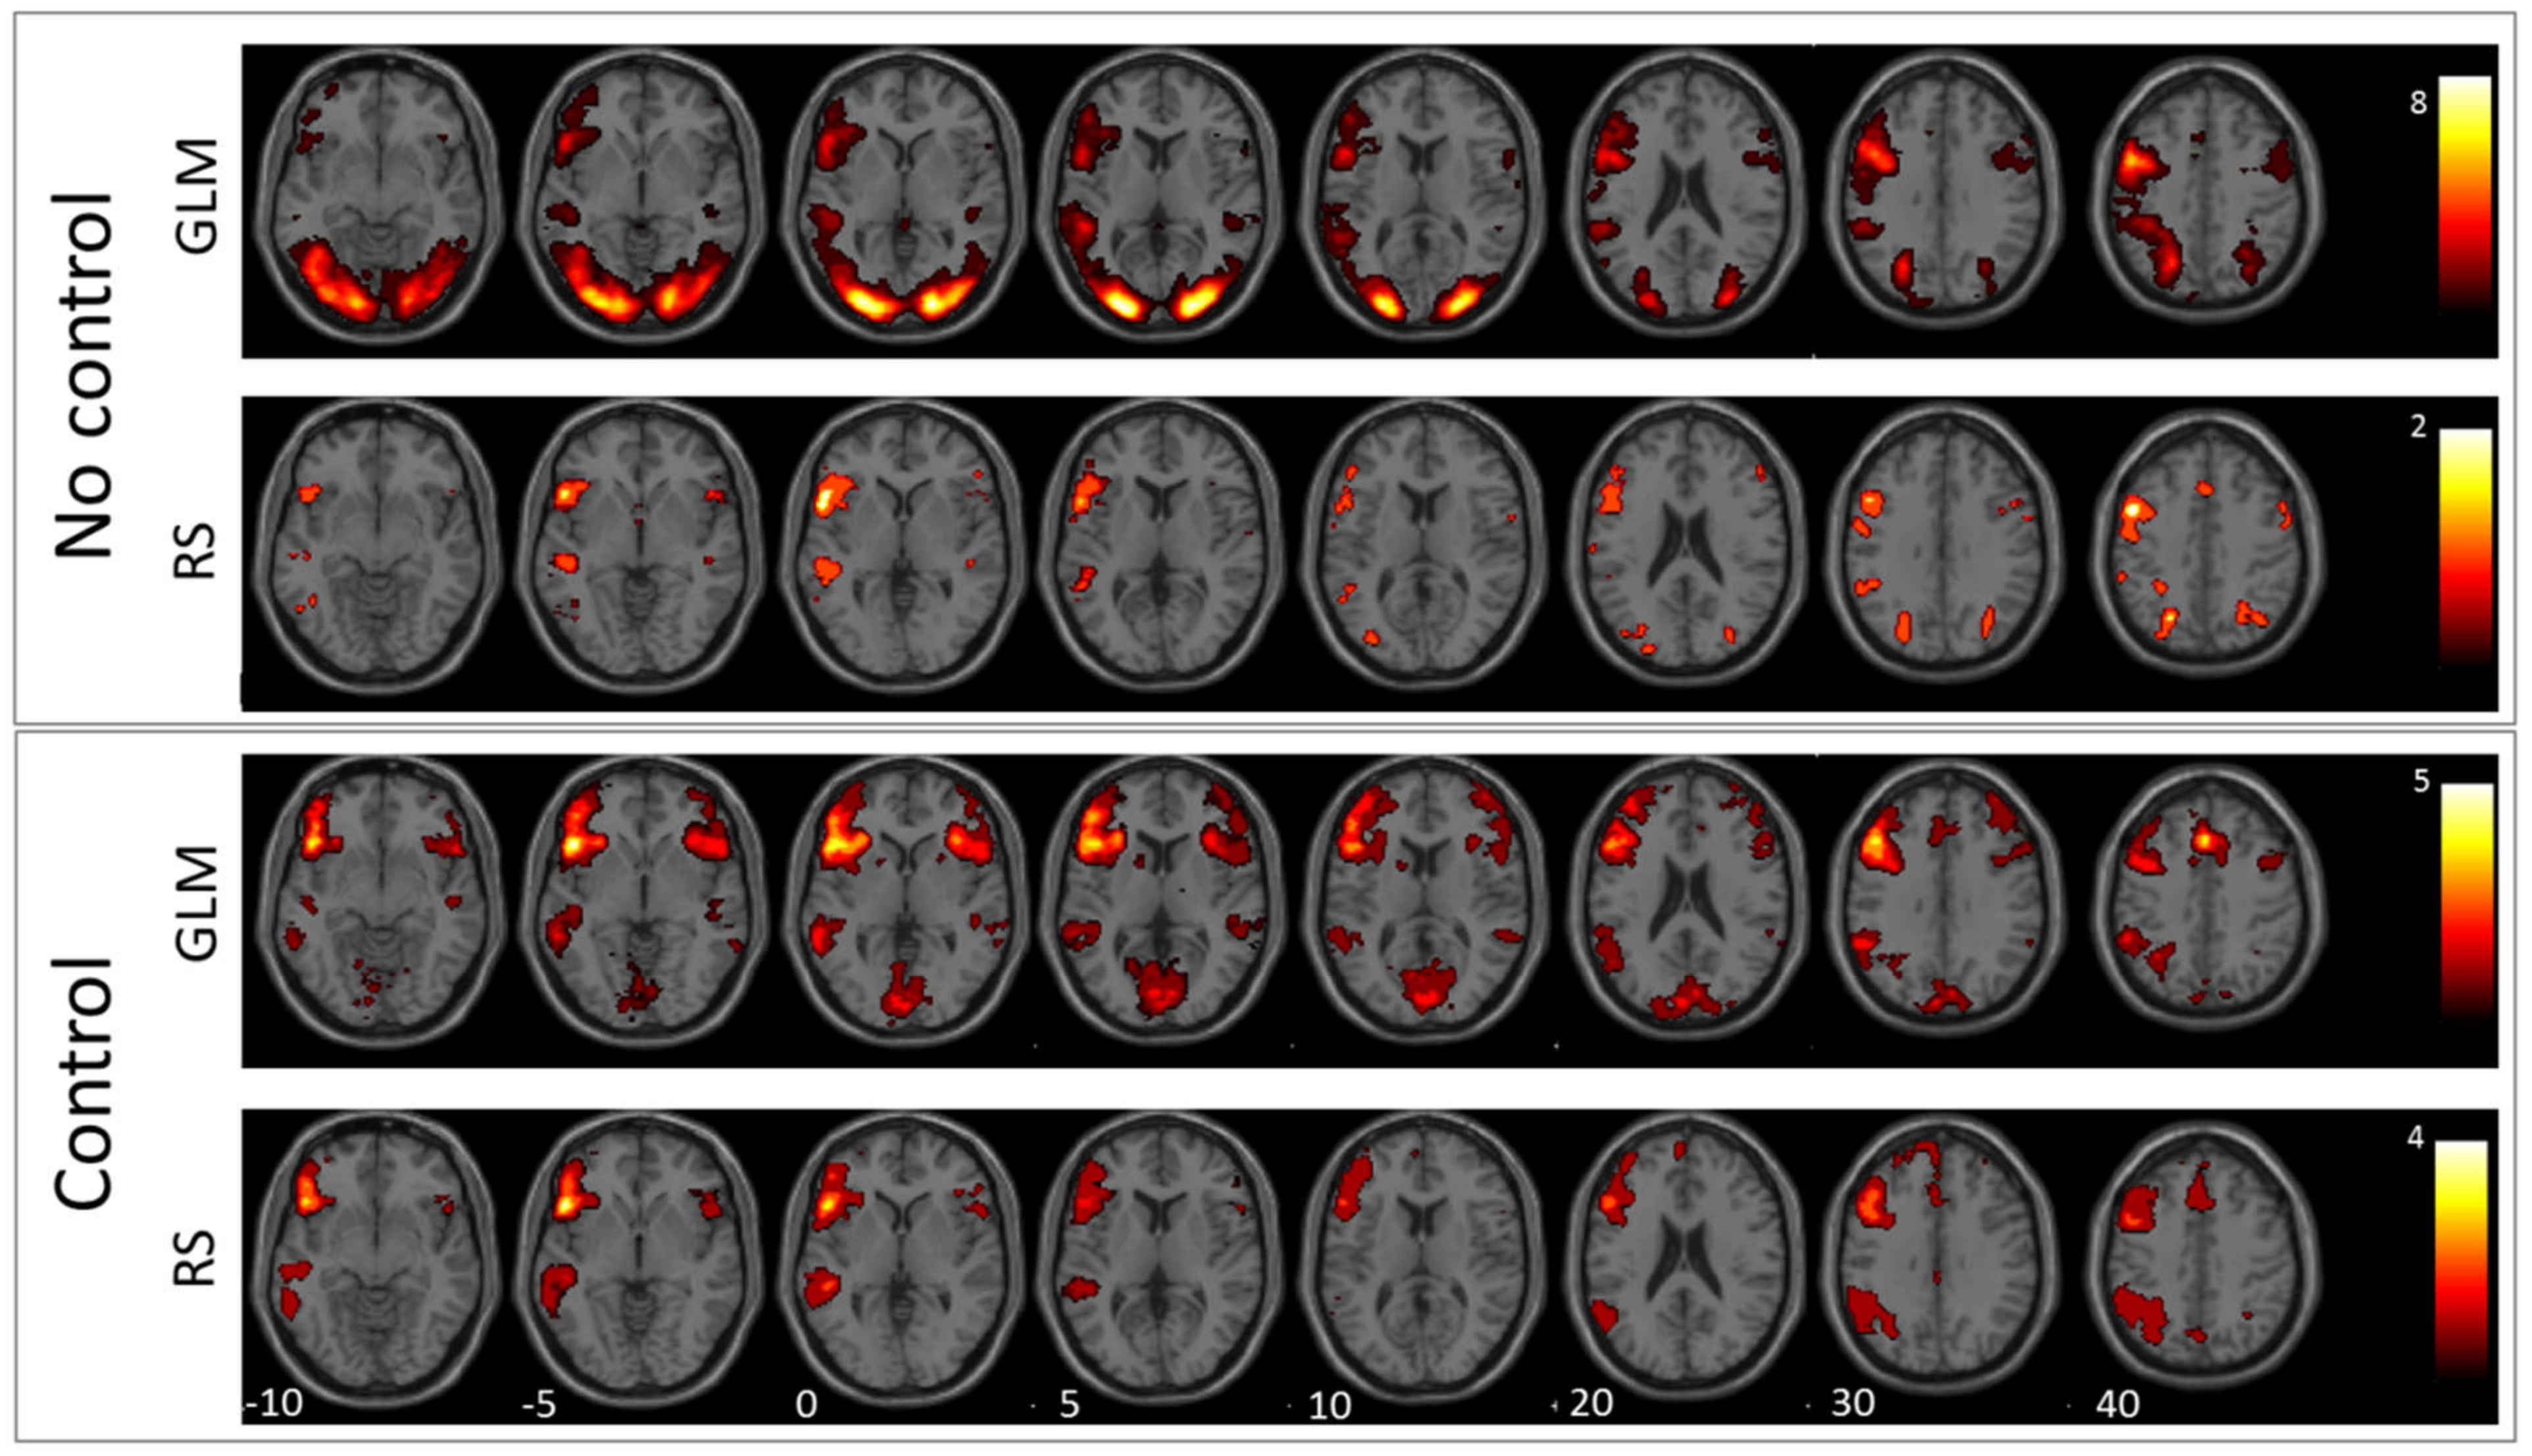

3.1. GLM Results

3.2. RS-fMRI Results